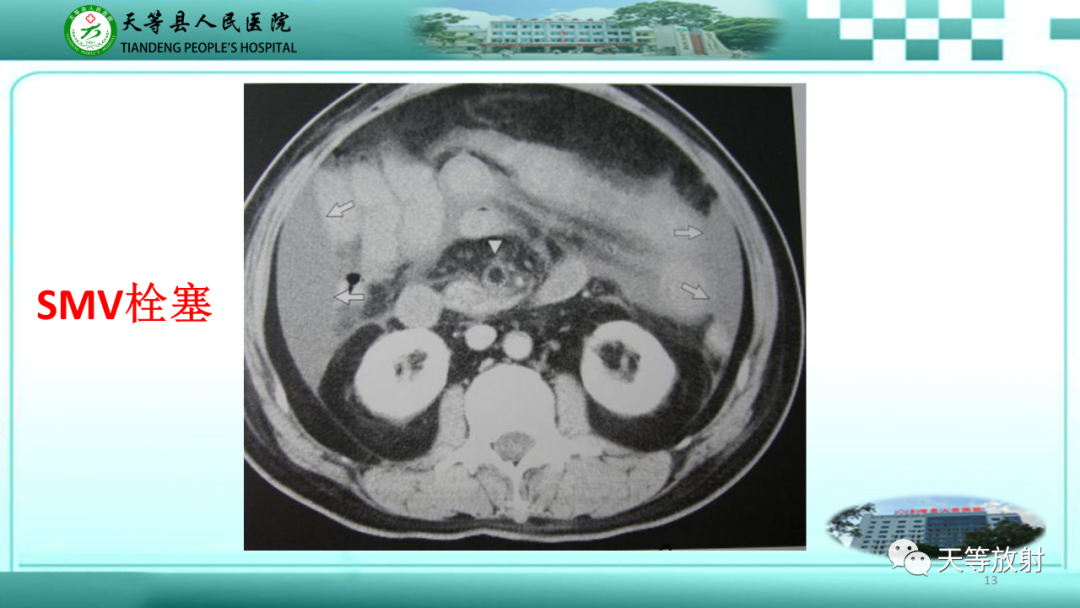

【PPT】缺血性肠病的影像学表现-13